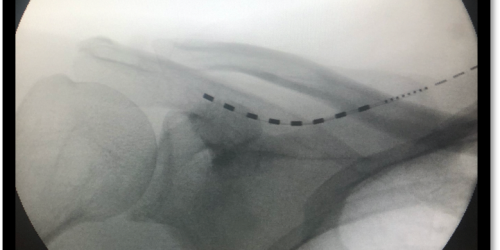

systemy neuromodulacji stosowane w terapii przewlekłego bólu, w tym SCS (Spinal Cord Stimulation), PNS (Peripheral Nerve Stimulation) oraz TSCS (Transforaminal SCS),

fiberoepiduroskopię – minimalnie inwazyjną procedurę umożliwiającą bezpośrednią wizualizację przestrzeni zewnątrzoponowej oraz rewizję kanału kręgowego,